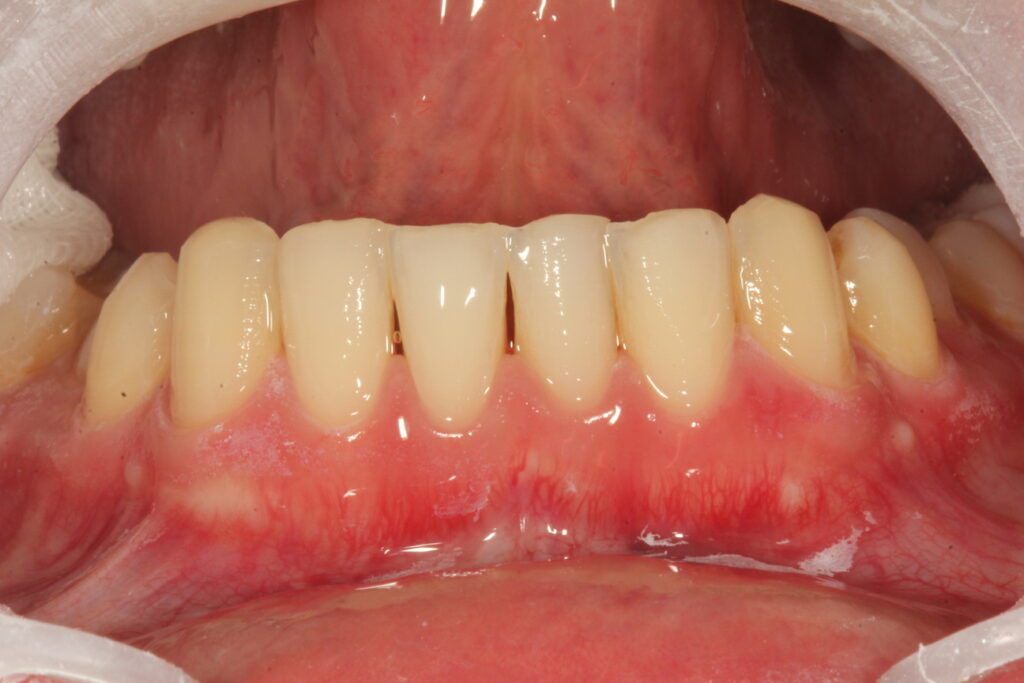

치료후 상태

이 분은 일본에 거주하는 분이었고, 직업이 매일 서비스직종이라 교정기를 하기가 어려웠습니다. 그리고 빠른 치료가 필요한 상태였습니다. 얼굴을 성형할 때에도 필요에 따라서 건강한 뼈를 깍고, 절개를 하기도 합니다. 외모지상주의는 아니지만 컴플렉스가 지나쳐서 사회생활이 어렵다면 이런 치아성형도 좋은 치료가 될 수 있다고 생각합니다.